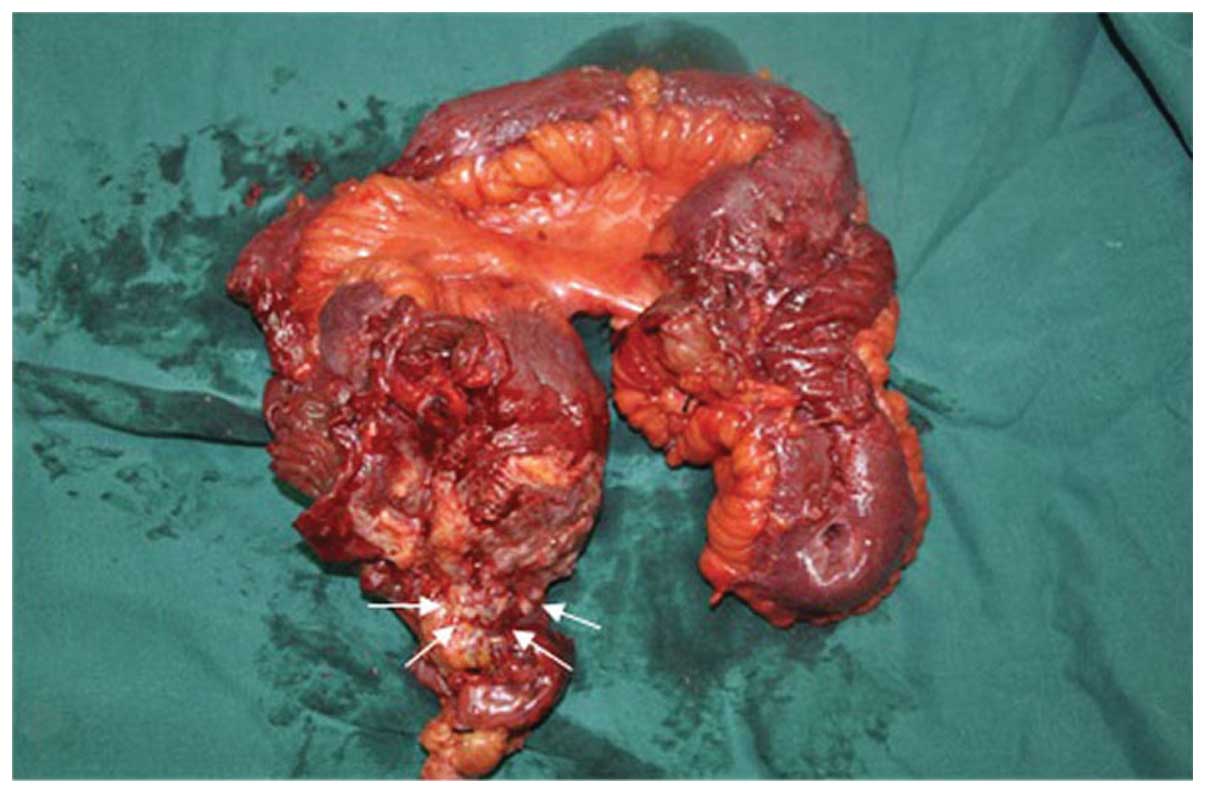

Asbestos is known to be a human carcinogen, but it is unclear if it is a cause of kidney cancer. With metastases beyond the regional lymph nodes. cancer has not spread to other parts of the body. mesothelioma is an uncommon type of cancer that occurs in the tissues covering your lungs or less commonly your tummy (abdomen). As is the case with pleural mesothelioma, these tumors often have spread too far to be removed completely. It is estimated that each year 2,000 new cases of mesothelioma are diagnosed. The patients suffering from this cancerous disease have prior exposure to asbestos, … This type of spread is called peritoneal metastasis or carcinomatosis and commonly occurs from cancers that originate from the colon, stomach, appendix, small intestine, ovary, pancreas and peritoneal mesothelioma.

cancer centers find a mesothelioma cancer center in ohio. The most common is pleural mesothelioma since asbestos fibers are usually inhaled. Surgery for peritoneal mesothelioma can be used to help ease symptoms or to remove the tumor from the wall of the abdomen (belly) and digestive organs. Peritoneal mesothelioma treatment by expert doctors at mercy. Asbestos likely reaches the abdomen through ingestion or via the lymphatic system.